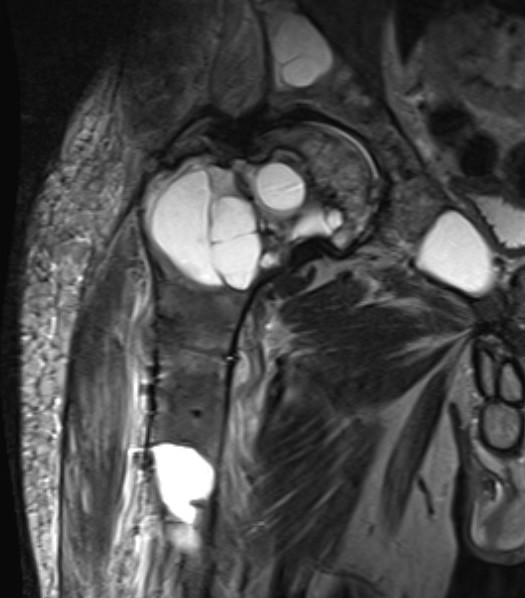

MRI

Low signal intensity T1 / High signal intensity T2